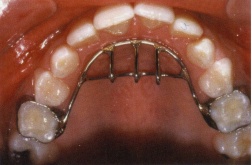

Cuối cùng, có thể sẽ phải cần dùng một khí cụ trong miệng để nhắc nhở trẻ. Khí cụ cố định thường được dùng hơn khí cụ tháo lắp. khí cụ gồm một cung lưỡi và một tấm chặn làm bằng dây thép không rỉ có đường kính lớn (0.9 – 1,0mm) được hàn vào hai khâu ở răng cối sữa thứ hai hoặc răng cối lớn vĩnh viễn thứ nhất hàm trên. Tấm chặn nhô ra (nhưng không được sắc bén) sẽ nhắc nhở trẻ không mút tay và trẻ cũng được giải thích rằng đây là vật nhắc nhở trẻ, không phải để trừng phạt trẻ để tránh gây vấn đề tâm lý cho trẻ. Sau khi trẻ ngưng mút tay, cần đeo khí cụ thêm 6 tháng nữa để đảm bảo thói quen được bỏ hoàn toàn.

Khí cụ cố định nhắc nhở trẻ không mút tay

Bệnh nhân cần phải được thăm khám kỹ để các bác sĩ đưa ra giải pháp điều trị thích hợp nhất. Tại Hệ thống Nha khoa Tân Hoàn Mỹ, để điều trị các tật này, bác sĩ sẽ dùng tấm chặn lưỡi cố định hoặc tháo lắp để ngăn chặn vị trí hoặc chức năng bất thường của lưỡi. Tấm chặn lưỡi làm bằng dây thép không rỉ có đường kính 0.8 mm. Vị trí của tấm chặn lưỡi có thể ở phía trước hoặc phía bên, tùy vào vị trí của lưỡi chêm giữa các răng trước hoặc răng sau.